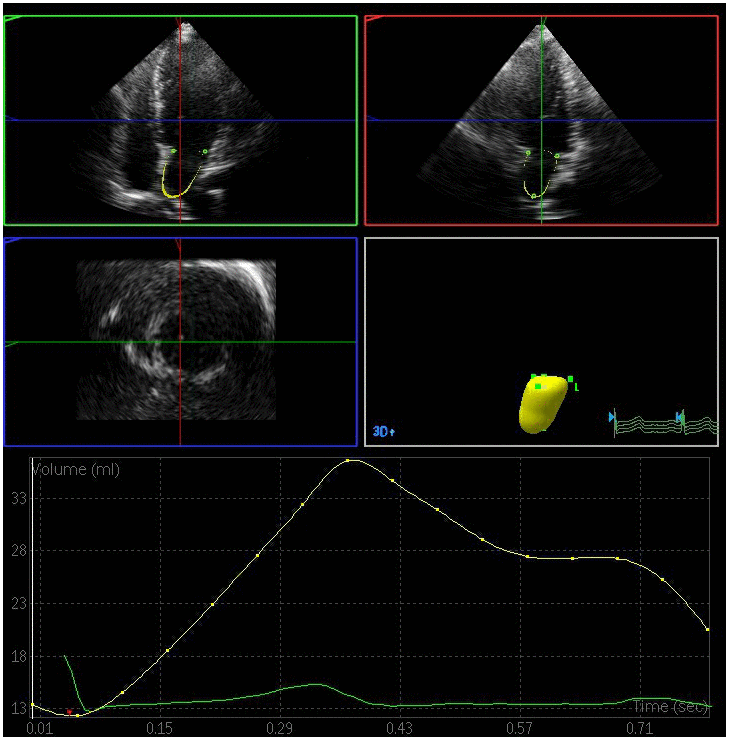

The left atrial maximum volume (LAVmax), left atrial pre-systolic volume (LAVp), and left atrial minimum volume (LAVmin) were significantly elevated in the DN and DM groups relative to the control group, whereas the total left atrial ejection fraction (LAEFt) and passive left atrial ejection fraction (LAEFp) were significantly lower in the DM and DN groups relative to the control group (P < 0.05) (Figures 1–3). The left atrial maximum volume index (LAVImax), left atrial pre-systolic volume index (LAVIp), and left atrial minimum volume index (LAVImin) were also significantly elevated in the DN group relative to the DM group, whereas the LAEFt and LAEFp parameters were significantly lower in the DN group relative to the DM group (P < 0.05). We also found that active left atrial ejection fraction (LAEFa) was significantly higher in the DN group relative to the DM and control groups (P < 0.05), whereas this parameter did not differ significantly between the DM and control groups (P > 0.05) (Table 3).

Figure 3. Left atrial volume quantification by RT-3DE of a case in DN group.